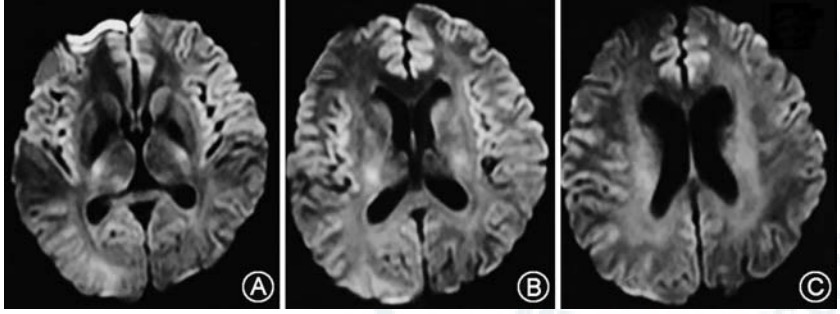

当氨在体内浓度甚高时,可导致脑水肿,诱发神经元和神经胶质细胞的变形、凋亡和坏死,还可以影响神经传导和大脑发育。头颅MRI多提示以额叶、岛叶皮质受累为主,急性发作期常见弥漫性脑水肿等,严重时可出现脑疝、梗死样表现。

对不明原因的呕吐、意识障碍及肝功能异常的患儿,特别是伴随头颅MRI提示额叶、岛叶皮质异常的,应高度警惕OTCD可能,必要时血尿代谢筛查,早期诊断、合理治疗是改善预后的关键。